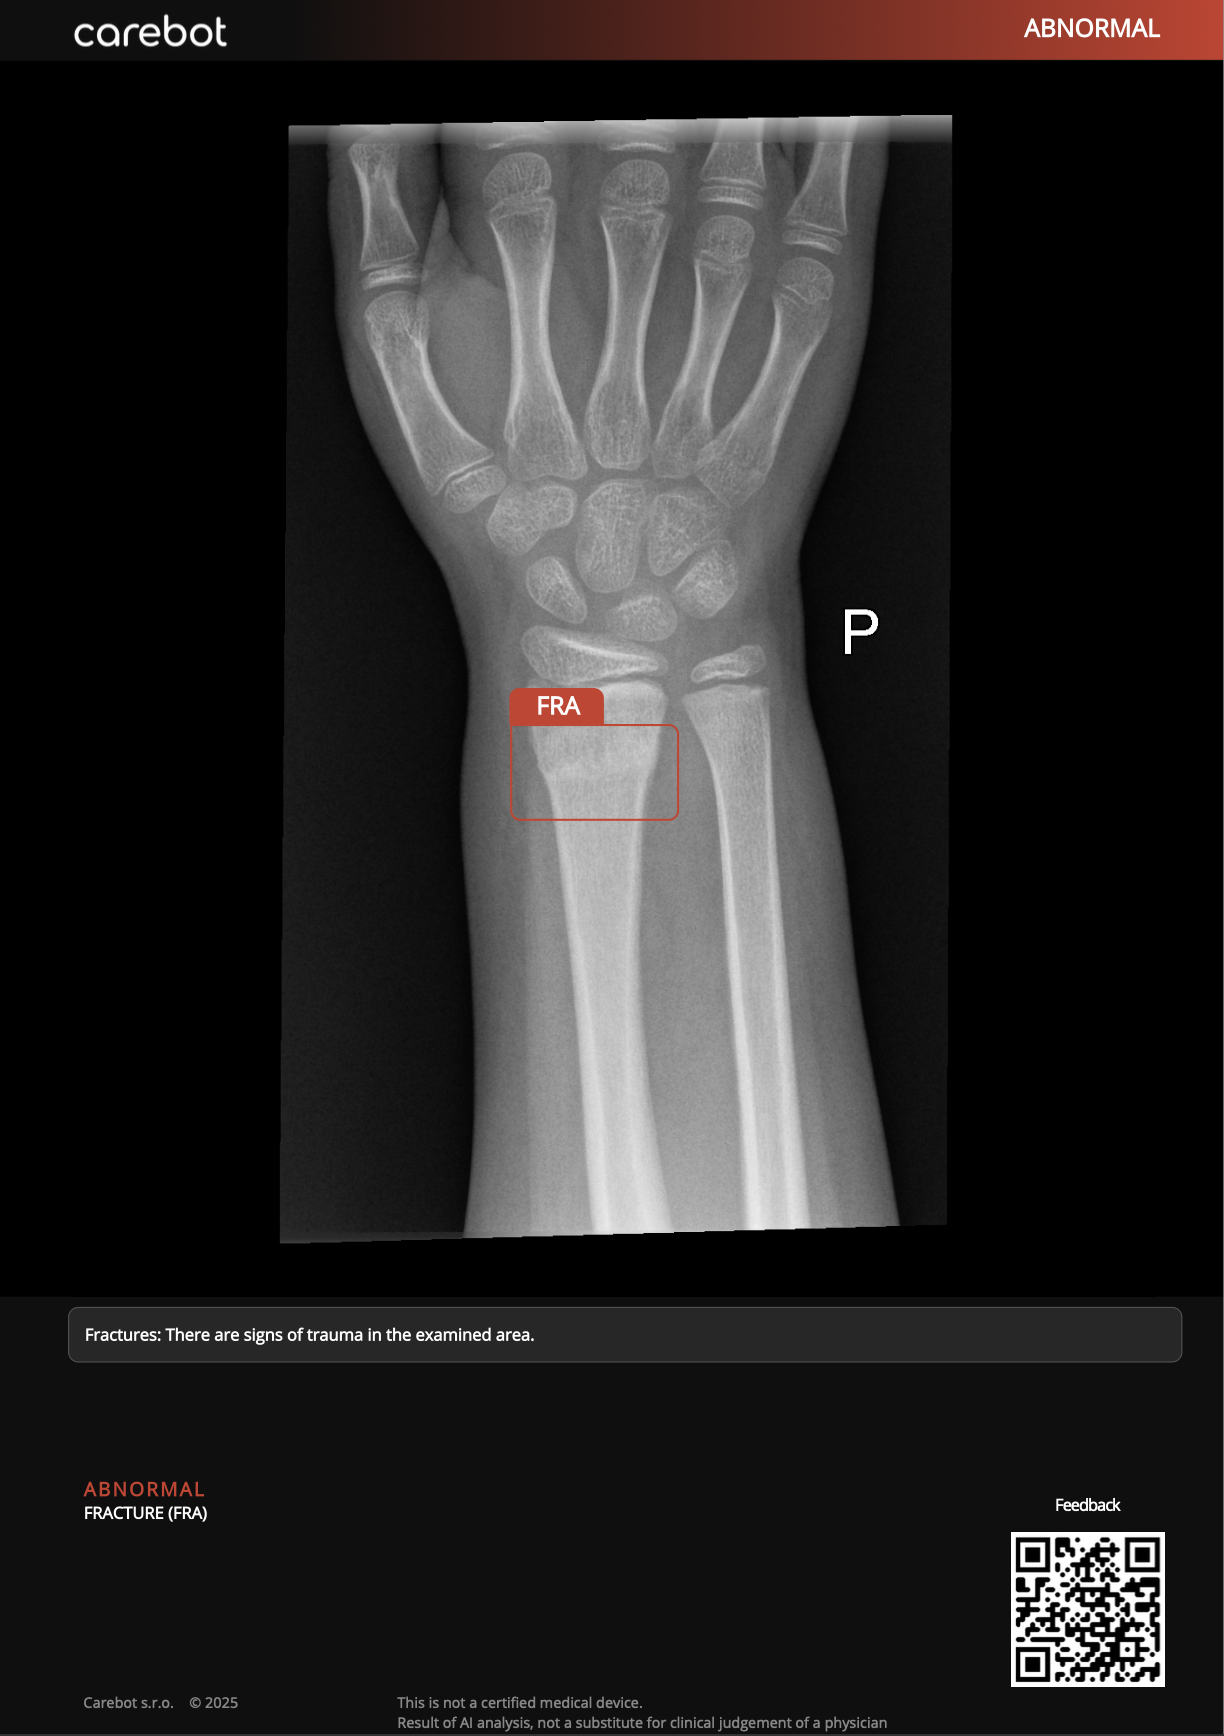

With summer coming on, it's worth noting that trampoline injuries generally peak between May and August. Given the increasing popularity of this activity, you may need to think about preparing yourself for a possible influx of cases.

Two Norwegian researchers have studied the 273 patients referred to the radiology department at Drammen Hospital between 2008 and 2010 after trampoline accidents, using mostly conventional radiography. Their findings are very revealing, and they have also scrutinized injuries due to sledging accidents. To find out more, visit our Digital X-Ray Community, or click here.